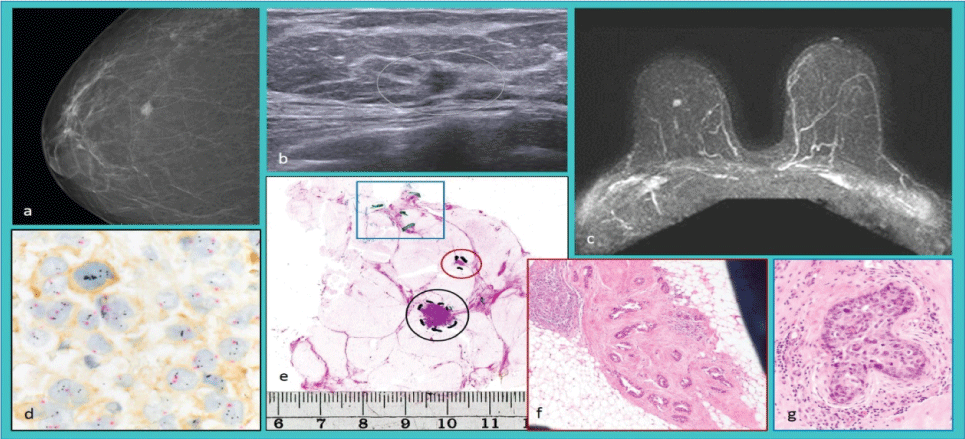

Radiologicallyunifocal

Figure 2: Radiologicallyunifocal invasive breast carcinoma. (a) Radiogram, (b) Sonogram, and (c) Magnetic resonance image. (d) Tricolor bright field in situ hybridization showing HER2 gene amplification. (e) Large-format histology of the surgical specimen shows the radiologically detected invasive tumor focus (black circle), an additional invasive focus (red circle), and structures of the in situcarcinoma (blue box). (f) Magnification of the additional invasive focus and (g) in situ component stained with hematoxylin and eosin.